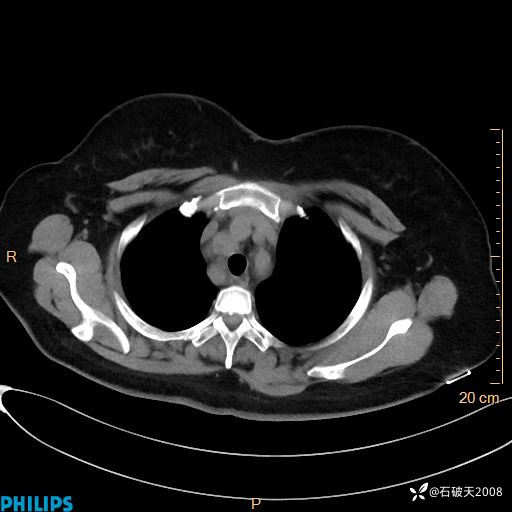

肺结节病?纵膈型肺癌?淋巴瘤?有点意思,欢迎围观

女 52岁 主 诉:咳嗽10余天,咳痰2天。

现病史:10余天前无明显诱因出现咳嗽,呈阵发性干咳,伴咽喉部发痒,无咽痛,无咳痰,无鼻塞、流涕、打喷嚏,无发热、畏寒、寒颤,无头痛、头晕,无胸闷、胸痛,无反酸、烧心,无腹痛、腹泻,无尿频、尿急,无皮疹等,在当地诊所求治,给予口服药物治疗(具体不详),病情无好转。遂在当地社区卫生服务中心开具口服药物治疗(具体不详),疗效欠佳。2天前出现咳痰,在我院门诊求治,行胸部CT提示肺部感染,建议住院,患者要求口服药物治疗,目前仍咳嗽、咳白色粘痰,白天量多,夜间自觉喉部喘鸣音,遂再次来院就诊,以“肺部感染”为诊断收入院。发病以来,神志清,精神可,饮食可,夜间睡眠差,大小便正常,近期体重无明显变化。

肺窗